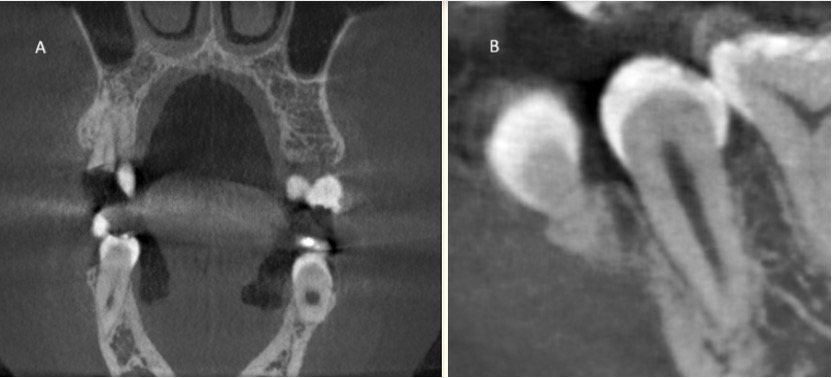

A CBCT A CBCT scan was performed prior to extraction as part of the patient’s standard care. [Figure 1]

Figure 1. A representative coronal slice from the preoperative CBCT scan (A), and a Sagittal close-up (B) view showing tooth #45 in situ (green arrows). This image illustrates the raw data used by the algorithm for 3D reconstruction.